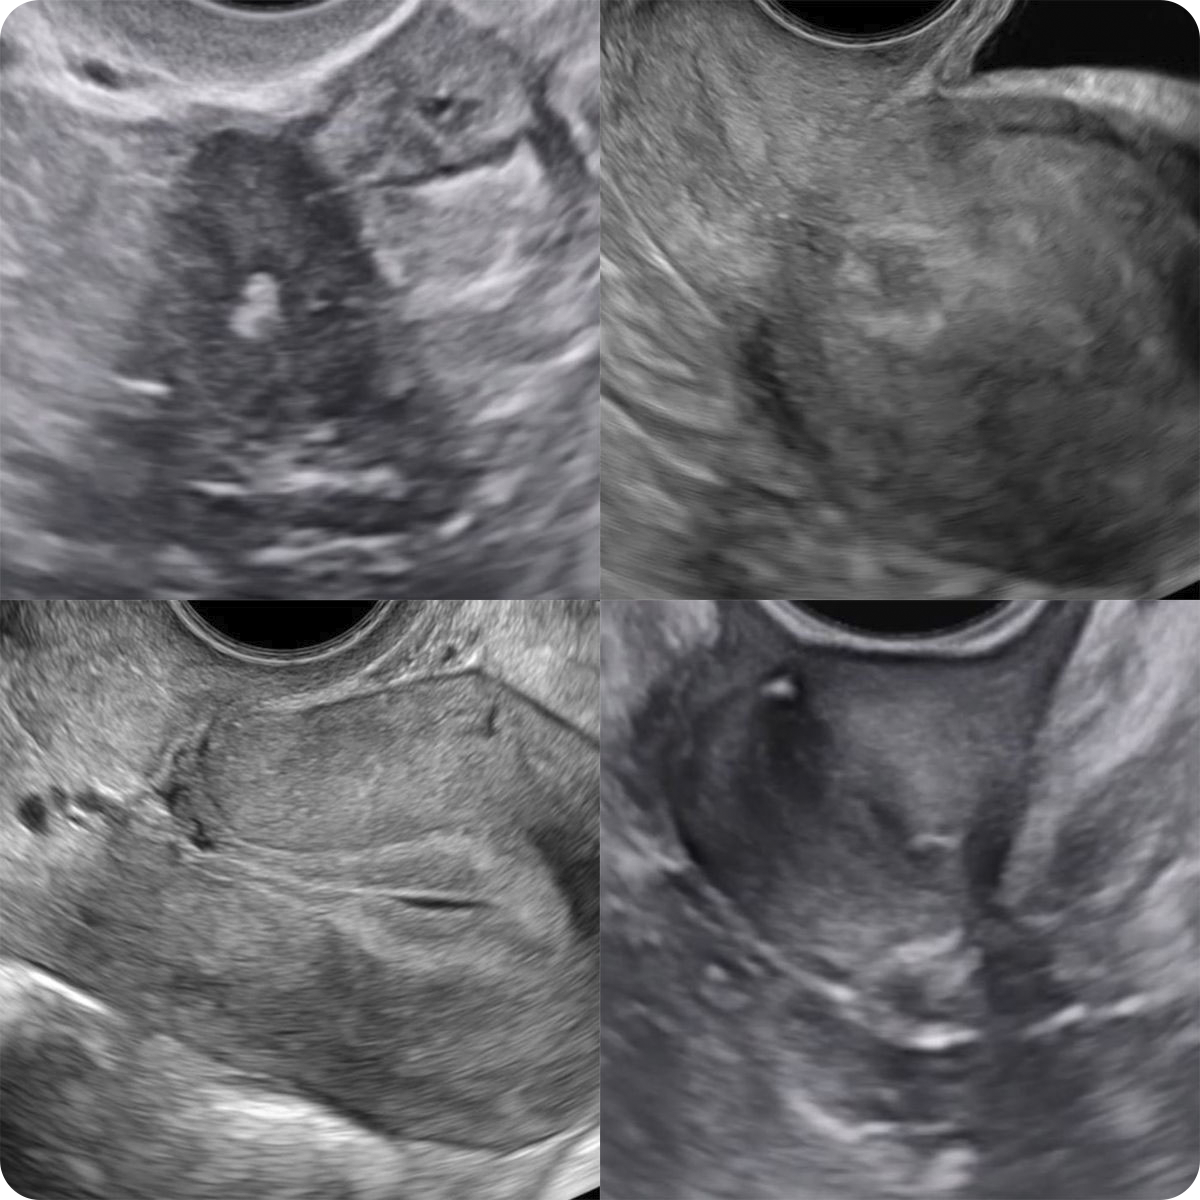

Эндометриоз малого таза. Эндометриомы

• Четыре шага исследования для выявления признаков глубокого инфильтративного эндометриоза по IDEA

• Глубокий инфильтративный эндометриоз переднего отдела малого таза

• Глубокий инфильтративный эндометриоз заднего отдела малого таза

• Ретроцервикальный эндометриоз

• Измерение очагов глубокого инфильтративного эндометироза

• Цветовая допплерография.

• Термины, слова, словосочетания

• Клинические случаи глубокого инфильтративного эндометриоза переднего, заднего отделов малого таза, ретроцервикального эндометриоза

• Спаечный процесс в малом тазу

• Описания. Заключения